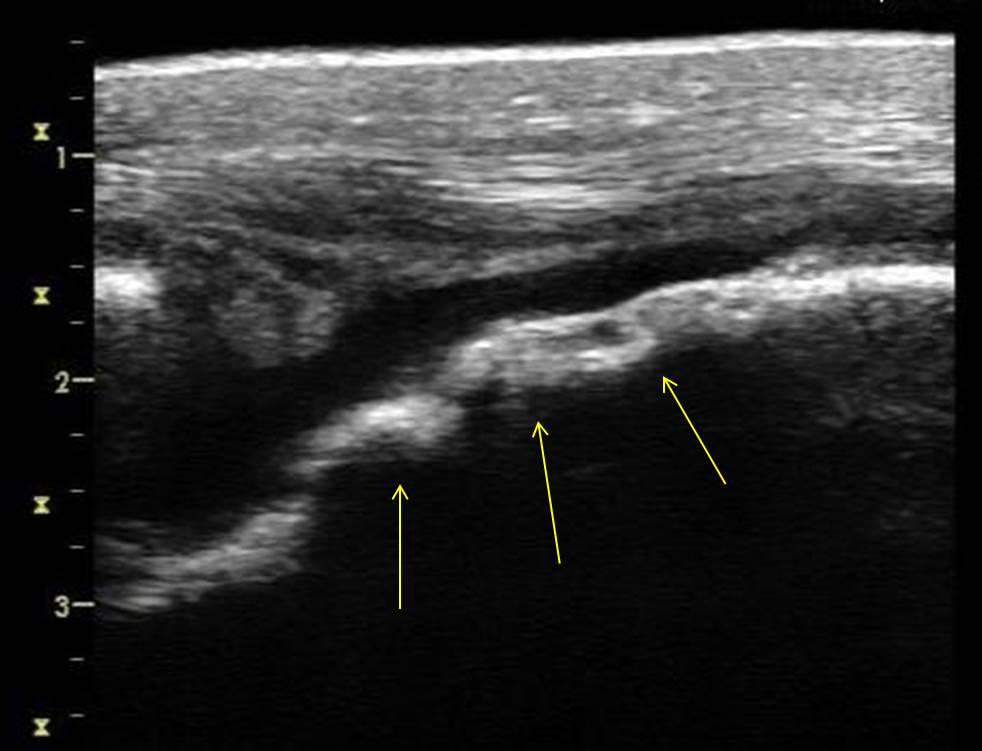

Figure 7 from Ultrasonography of the Canine and Equine Stifle Joint

Figure 7 from Ultrasonography of the Canine and Equine Stifle Joint Horse Stifle Ultrasound the equine stifle is a large, complex region and its ultrasonographic examination requires a thorough. stifle injuries are increasingly recognized as a major cause of hind limb lameness in a normal horse. ultrasound can be useful to detect osteochondrosis lesions of the trochlear ridges in juvenile horses that are normal. ultrasonography has tremendously improved our ability. Horse Stifle Ultrasound.